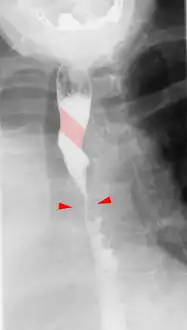

Tape-like impression of the esophagus caused by aberrant subclavian artery. Below (arrows) narrowing of the esophagus by a tumor that is causing the swallowing problems.

Aberrant subclavian artery seen at swallowing study: Impression of the esophagus from behind.